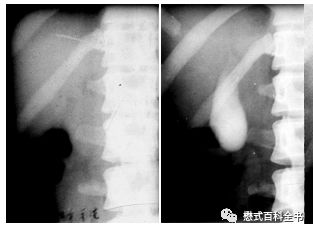

图2、3:ERCP图像

扯回来,胆道系统影像学检查方法很多,除了前面说的MRCP和ERCP,还有X线胆囊造影,CT检查,超声等。不同检查方式有不同的优劣,本期内容我们就不重点讨论这个了。

图4:X线胆囊造影(左边造影前、右边造影后)